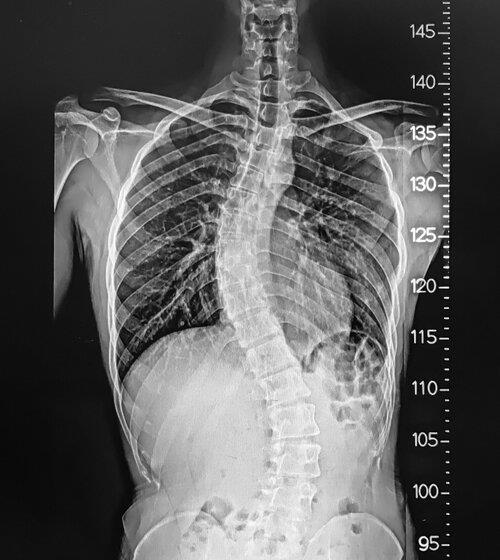

To reduce Neck Pain, in Phoenix Dr. Andrew Chung finds the problem using the x-ray test and provides suitable treatment with or without surgery. He gives 100% effort while performing the cervical surgery. He knows how to use the latest science-based technique while carefully removing damaged nerves or tissues. In the Banner Health Clinic, he has experience in dealing with patients and using effective methods to make treatment pleasant and comfortable for the patients. For more details, click on the website.